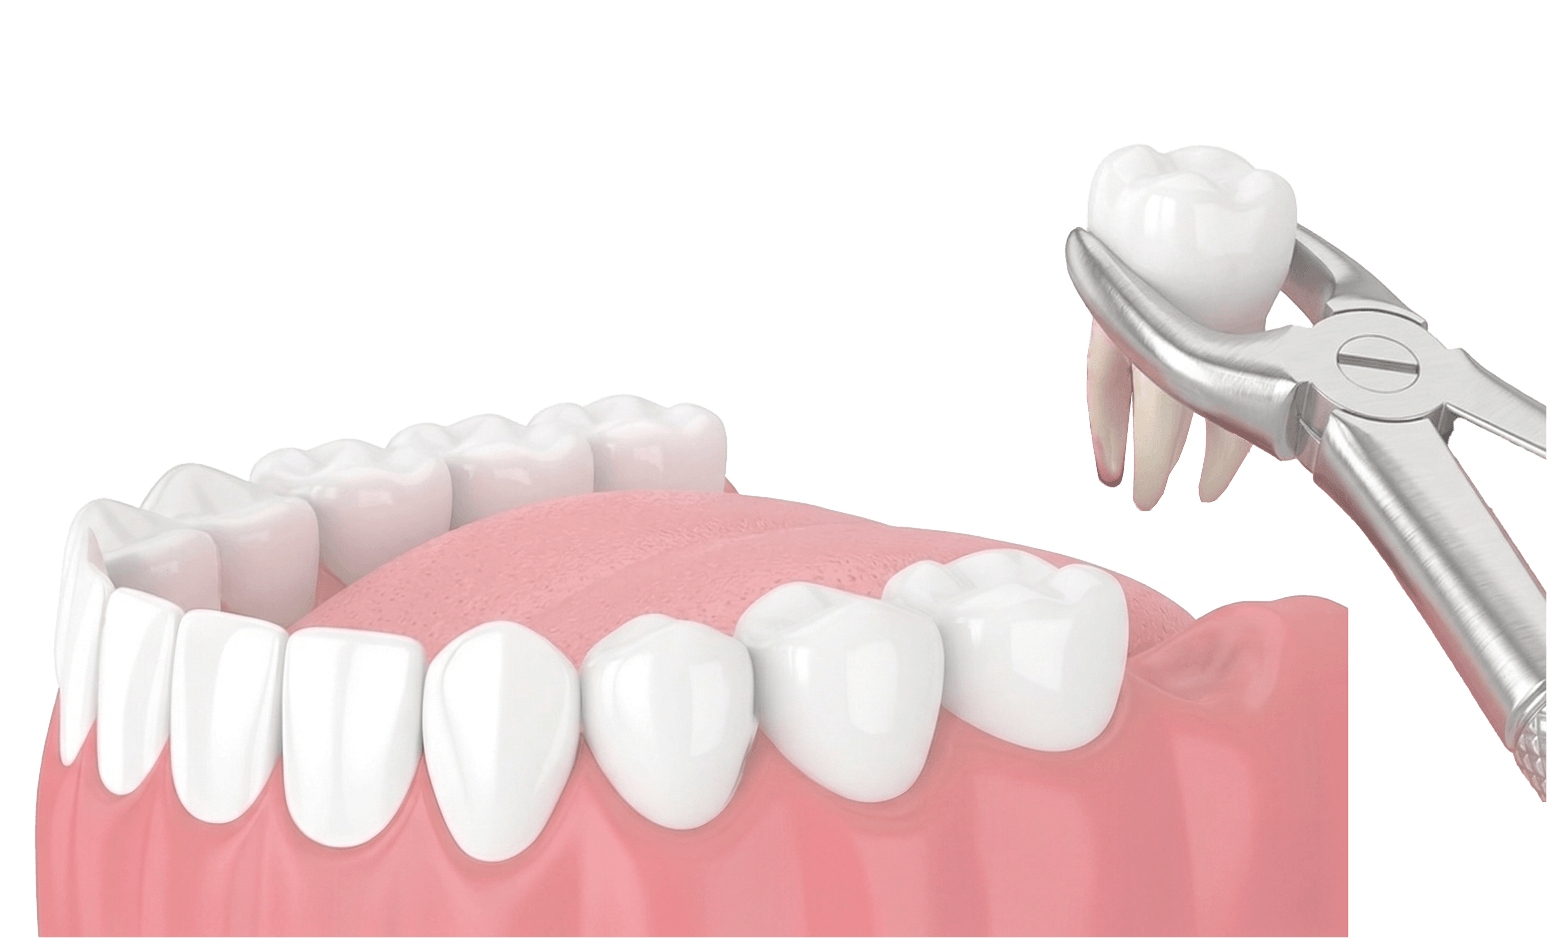

專業處理簡單及複雜橫生智齒,解決牙痛與發炎困擾。結合先進 3D 影像技術,提供安全、微創的拔牙體驗。

在無痛環境下進行微創拔除,必要時將牙齒分割取出以保護骨骼。

徹底清理術區並縫合傷口(如需要),以幫助止血與癒合。